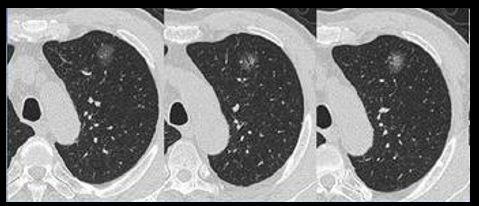

肺结节:影像(主要指CT)发现的直径<3cm的类圆形阴影。结节分为纯磨玻璃结节、混合密度结节和实性结节。

结节的3种密度类型